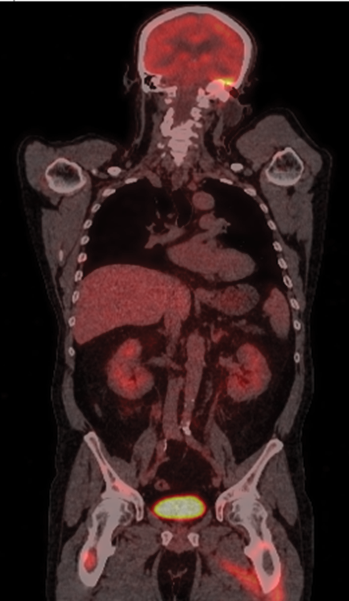

Figure 2. Whole-body PET scan (coronal view) reveals hypermetabolic foci in the petrous pyramid of the left temporal bone, with radiotracer accumulation in the brain, mediastinum, adrenal glands, pancreas, kidneys, and multiple bone lesions, particularly in the femurs

A whole-body fluorodeoxyglucose positron emission tomography (PET) scan was conducted. The PET scan revealed extensive disease involvement in the left petrous pyramid and widespread disease across various other organs and bones (Figure 2). These findings were consistent with Lugano stage IV lymphoma.